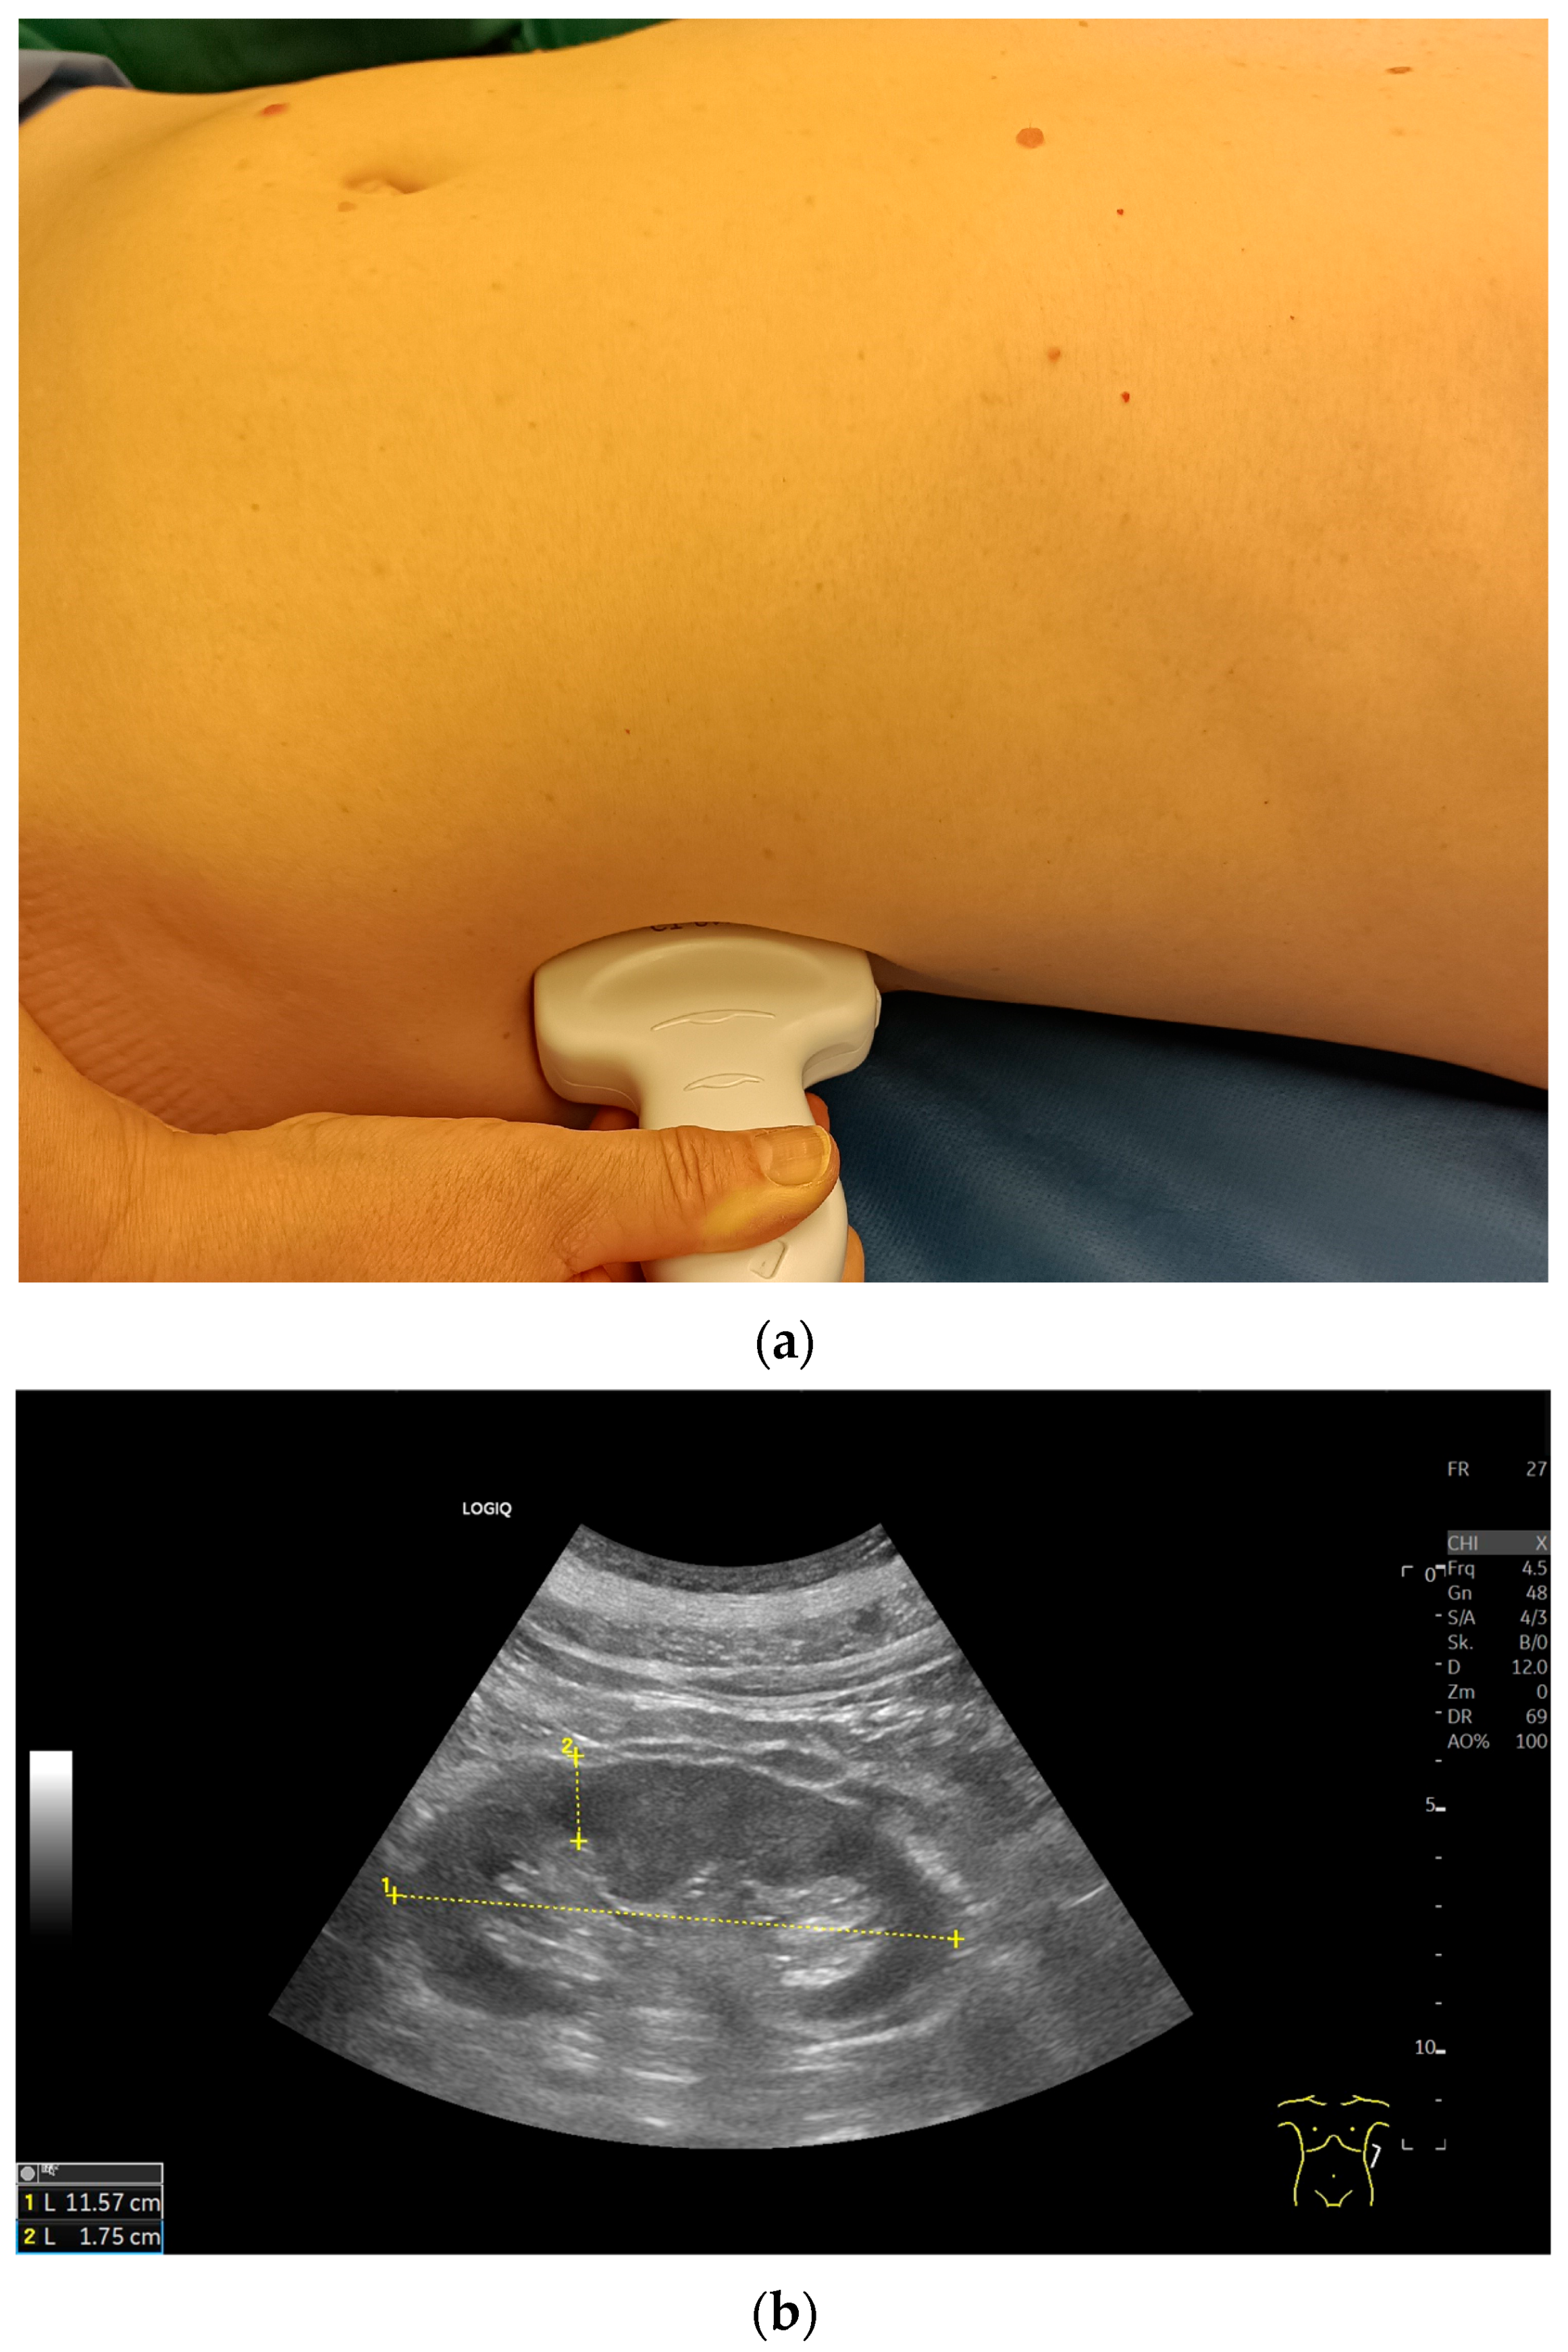

Imaging Techniques and Protocol